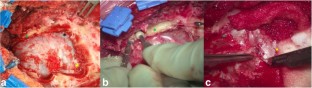

Fig. 2

A short video showing the resection of a petroclival meningioma through an extreme lateral supracerebellar infratentorial approach is added. (MP4 417,221 kb)